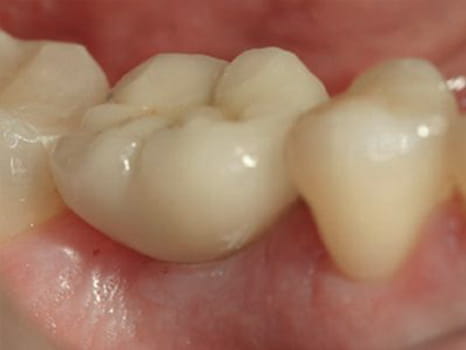

Implantat-nachher

...und nach Eingliederung im Mund